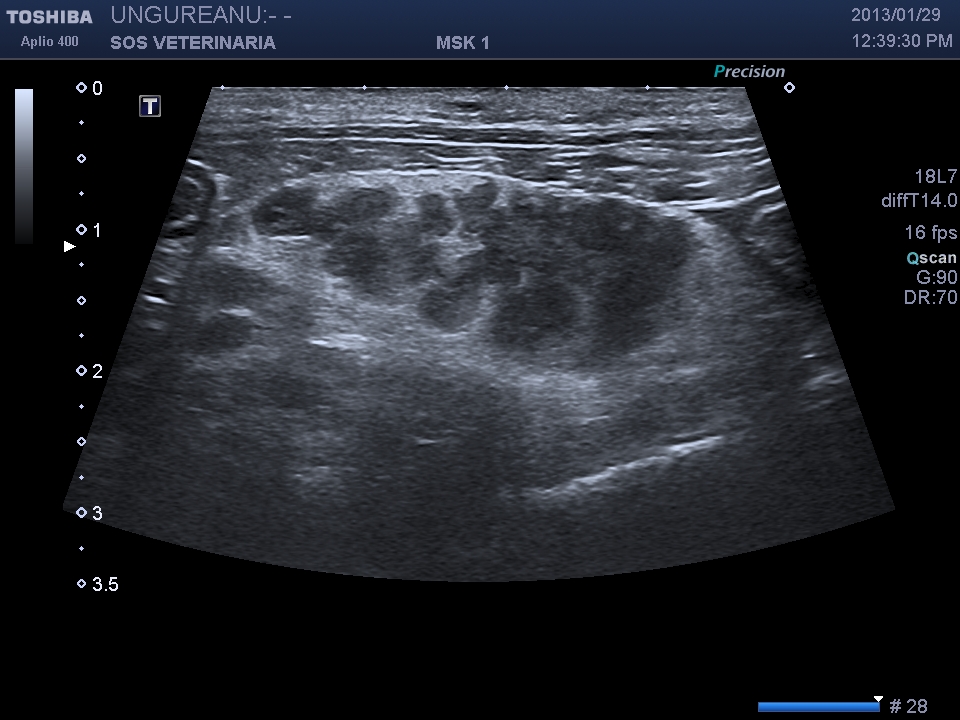

:COLANGIOCARCINOMA

Gatta comune europea 16 aa DSC_8846

evidente la severa  dilatazione delle vie biliari intraepatiche( visualizzabile nelle fasi piu’ avanzate dei processi cronici) ,la massa prende origine dal  coledoco e ha generato nel corso della malattia una progressiva distenzione delle vie biliari extraepatiche che raggiungono gradi di dilatazione abnormi e rimangono riconoscibili per la parete ispessita , come in questo caso possono essere presenti calcoli o calcificazioni della massa .

.Nonostante la gravita’ del processo il soggetto ha convissuto con la malattia diversi mesi